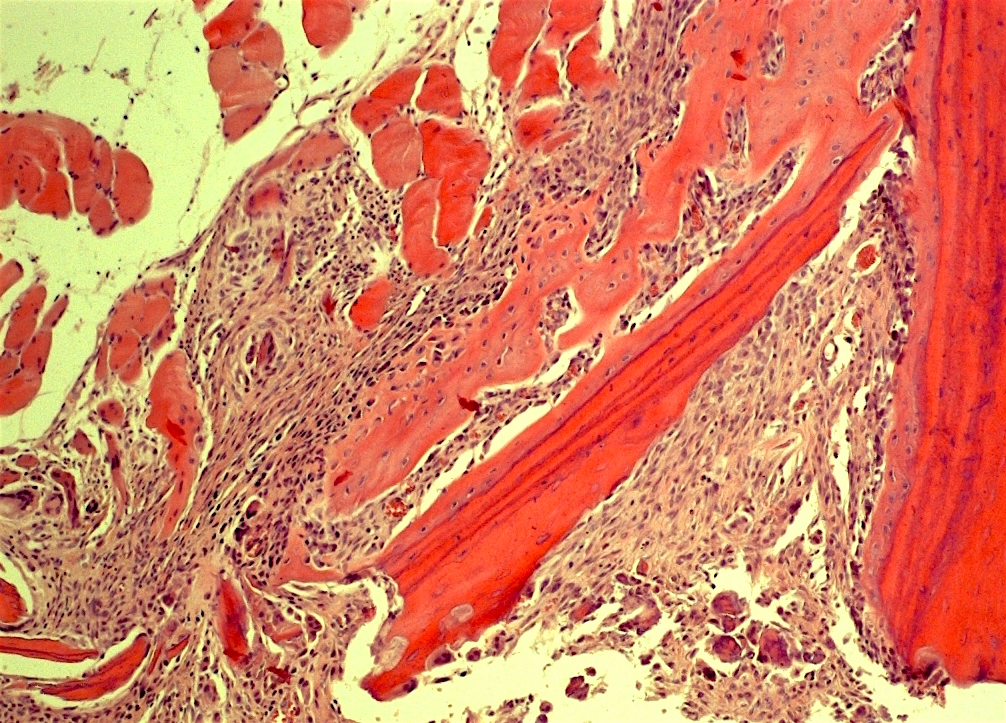

Трансплантируемый в соединительную ткань фрагмент кости, который был предварительно декальцинирован, быстро заморожен и обезвожен в большинстве случаев индуцирует эктопическое костеобразование.

Самое главное чтобы в трансплантат врастали сосуды.

Пусть даже самых мелкий из капилляров будет в этой области, на нем начнут образовываться вытянутые клетки - периваскулярные.

Их обнаружила Марчанд и назвала их адвентициальными.

Было доказано что осколки живой кости можно использовать для организации небольших центров остеогенеза и в 1972 году Хэм и Гордон сравнили осколки живой кортикальной кости подсаженные в мышцу и трижды замороженные и оттаявшие, чтобы убить все клетки.

Во втором случае образования кости не происходило.

Она образуется от осколков с живыми остеоцитами.

Губчатая кость имеет много остеогенных клеток, а кортикальная нет.